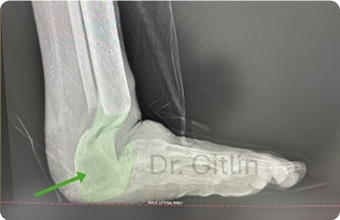

The X-ray below shows in red color the area that we needed to fill with bone. In order to achieve this we cut the leg bone called the tibia and pulled a piece of that bone downward to lengthen the bone and then we turned the bone with the external fixator to replace the heel.

The picture below shows in the green color all of the new bone we created. Even though it will never look like the actual bones and joints it still functions to give the patient a usable limb. Under this X-ray you can see a picture of the patients foot after surgery. The patient is now over two years after surgery and can normally walk and run with his children.